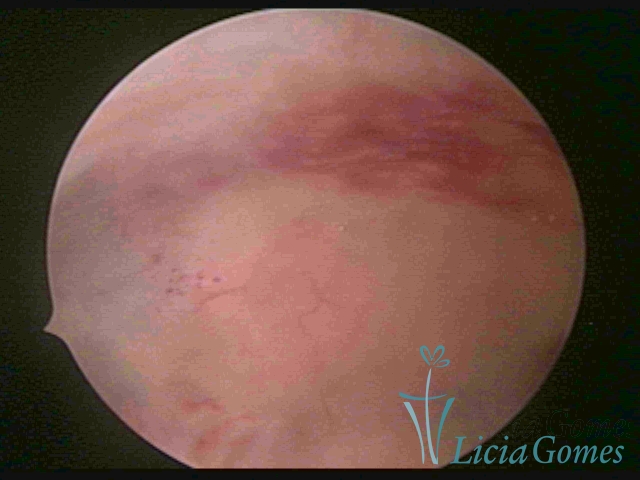

The surface of the endometrium may present changes such as a red punctuate forming vascular balls, a smooth, hypervascularized endometrium or intensely presenting red areas, with accurate edges and yellowish white spots in its interior, providing a "STRAWBERRY PEEL" aspect, a pale yellow color of fundic and lateral commissures, in contrast with the intense red color present in the walls.

On Advanced chronic endometritis, a thin endometrium is observed, presenting denude, sometimes ulcered areas of a greenish gray color with micro varicosities presenting a hazel color, more accentuated in the cornual regions (vascular dystrophy.)